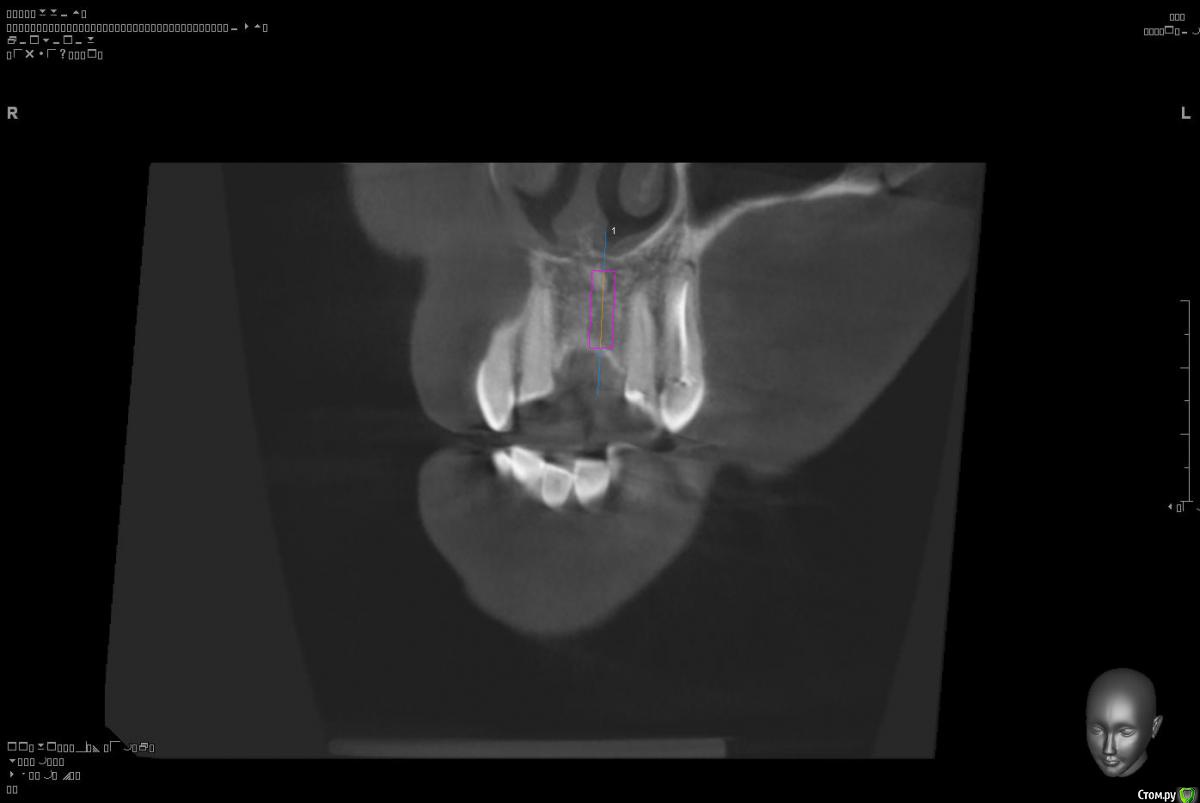

Platon Опубликовано 10 января, 2016 Поделиться Опубликовано 10 января, 2016 Здравствуйте.Помогите с планированием начинающему.Пациентка 38 лет. отсутствует 21. визуально в области 21 провал (фото нет, пока только кт). ходит с акриловой "птичкой"ортопед говорит: ставь, она к эстетике не будет предъявлять претензий))). с чем мне не хочется соглашаться(система ALPHA BIOкак правильно поступить?какие варианты рассматриваю:1. имплантация 3,75 на 11.5 SPI. ,+ временная коронка. Без какой либо пластики.2. костная пластика (мембрана,ксено,) без имплантации, сст, капа на 4 -6мес. потом имплантация + временная коронка3. имплантация, сст , временная коронка С учетом обстановки, прессинга, отсутствия опыта в аугментации, склоняюсь к третьему варианту. заранее спасибо за советы!удачного дня! Ссылка на комментарий

Platon Опубликовано 31 января, 2016 Автор Поделиться Опубликовано 31 января, 2016 Продолжение.не судите строго за фото, первый раз вообще фоткаю операцию)спасибо за советы.По порядку. После того, что мне написали, я решил все -таки уговорить на конусный имплантат (3.7-11.5 ImplantDirect). Также ортопед не хотел делать временную коронку, сказал что сделает каппу, птичку в топку -тоже сделали. Слизистая в области 21 была в рубцах. Исходя из этого всего я решил, коль временной коронки не будет, то сст подсаживать тоже не стану пока,(ортопеда уговаривал сделать временную коронку)))- торк был хороший 35-50н) для того чтобы сст попрактиковаться, но(((.в итоге, анестезия, разрез, сверло пилотное и сверло 2.2, далее расщепление с помощью набора майзенгер с использованием спредеров до нужного диаметра, установил имплантат, торк контролируемый, можно было подобрать любой) в итоге оставил 35. заглушка, совсем немного ксено, мембрана, ушился. ждем. Будет что-то типо каппы которая слегка отдавливает десну,формируя сосочки. не знаю, ни разу такую еще не видел.планирую на этапе раскрытия все-таки сст и временную коронку увидеть.вот. через 4 мес. выложу, что получилось) Если есть советы, критика, всему буду рад, спасибо 3 Ссылка на комментарий